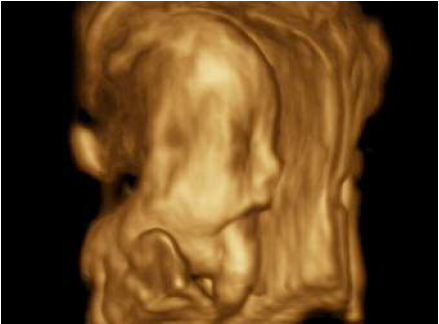

Paciente de 20 años de edad, procedente del estado Carabobo, de ocupación asistente administrativo, primigesta, con embarazo de 21 semanas, quien acude a la unidad de perinatología del Hospital materno-infantil “Dr. José María Vargas” para evaluación morfogenética del segundo trimestre. Sin antecedentes familiares y personales pertinentes, con un solo control prenatal para el momento de la evaluación. Se realizan estudios de laboratorio de rutina prenatal sin alteraciones y el cariotipo reporta feto 46 XY normal. El estudio ecográfico perinatal revela embarazo de 21 semanas con feto único, longitudinal, podálico, posición derecha anterior con imagen que emerge de cavidad bucal con aspecto ecomixto, lobulado (fig. 1, 2, 3) y polihidramnios con índice de líquido amniótico ILA P>95, planteándose como diagnósticos aparte de encefalocele anterior, épulis, epignatos, hamartomas entre otros tumores que protruyen a través de la cavidad oral. Resto del examen sin alteraciones. La finalización del embarazo se realiza por vía vaginal en la misma semana. En la autopsia perinatal se evidencia gran masa oral (fig. 4 y 5), con un componente quístico y sólido secundario debido al conducto esfenoideoccipital persistente. El contenido del encefalocele basal además de meninges y líquido cefalorraquídeo fue el lóbulo occipital, parte del tronco encefálico y la glándula pituitaria (fig. 6).

La falta de desarrollo de los núcleos de osificación de la porción basilar del occipital y la parte posterior del esfenoide dio origen a un canal que ocasiona la herniación de estructuras como el lóbulo occipital, meninges, líquido cefalorraquídeo, tallo cerebral y la glándula hipófisis. En la literatura no existe reporte de diagnóstico antenatal previo a éste. Los casos descritos de persistencia de canal craneofaríngeo se han puesto de manifiesto como hallazgo ocasional en la vida adulta. Se evidencia asociado a otras alteraciones como síndrome de Arnold Chiari y agenesia del cuerpo calloso, incluso, presentando manifestaciones clínicas como rinorrea persistente, meningitis y distrés respiratorio (8,9).